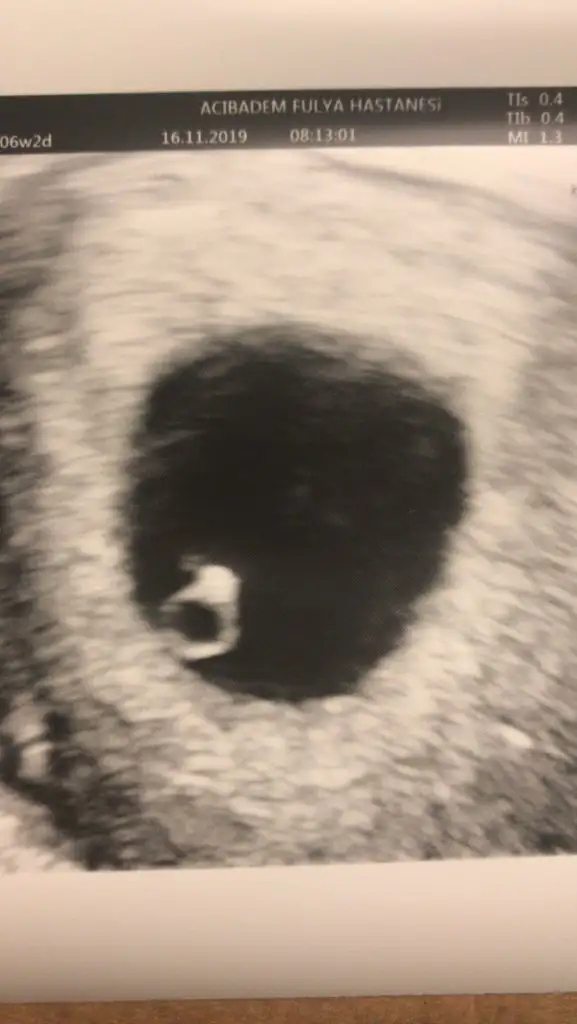

Selamlar doktordan geldim şimdi. Ultason resmi bildiniz tek taş yüzük şeklinde kalp atışı var gördük. Bir sorun yokmuş günlük hayatına devam et 6 hafta sonra gel dedi. bir sürü tahlil istedi. Daha yaptırmadım 6 hafta dolmasına yakın yaptıracağım.değerler güncel olsun istedim. Bu arada benim çikolata kisti aynen sağ tarafta duruyor. Soldan yumurtlama olmuştu. Kist gebelik sürecine engel değil. Kistin olması zorunlu sezeryan anlamına gelmiyor. Kistini unut gitti gibi düşün artık eriyecek o dedi. Kistin tedavisi gebelikmiş bu arada

Hayırlı olsun doktora giderken sat a göre 5+3 günlük hamileyim sanıyordum. 4+6 göründüler. Sadece keselerini gördük. 22 Kasım da yani 6+2 de kendilerini ve kalp atışlarını duymak için gideceğiz.